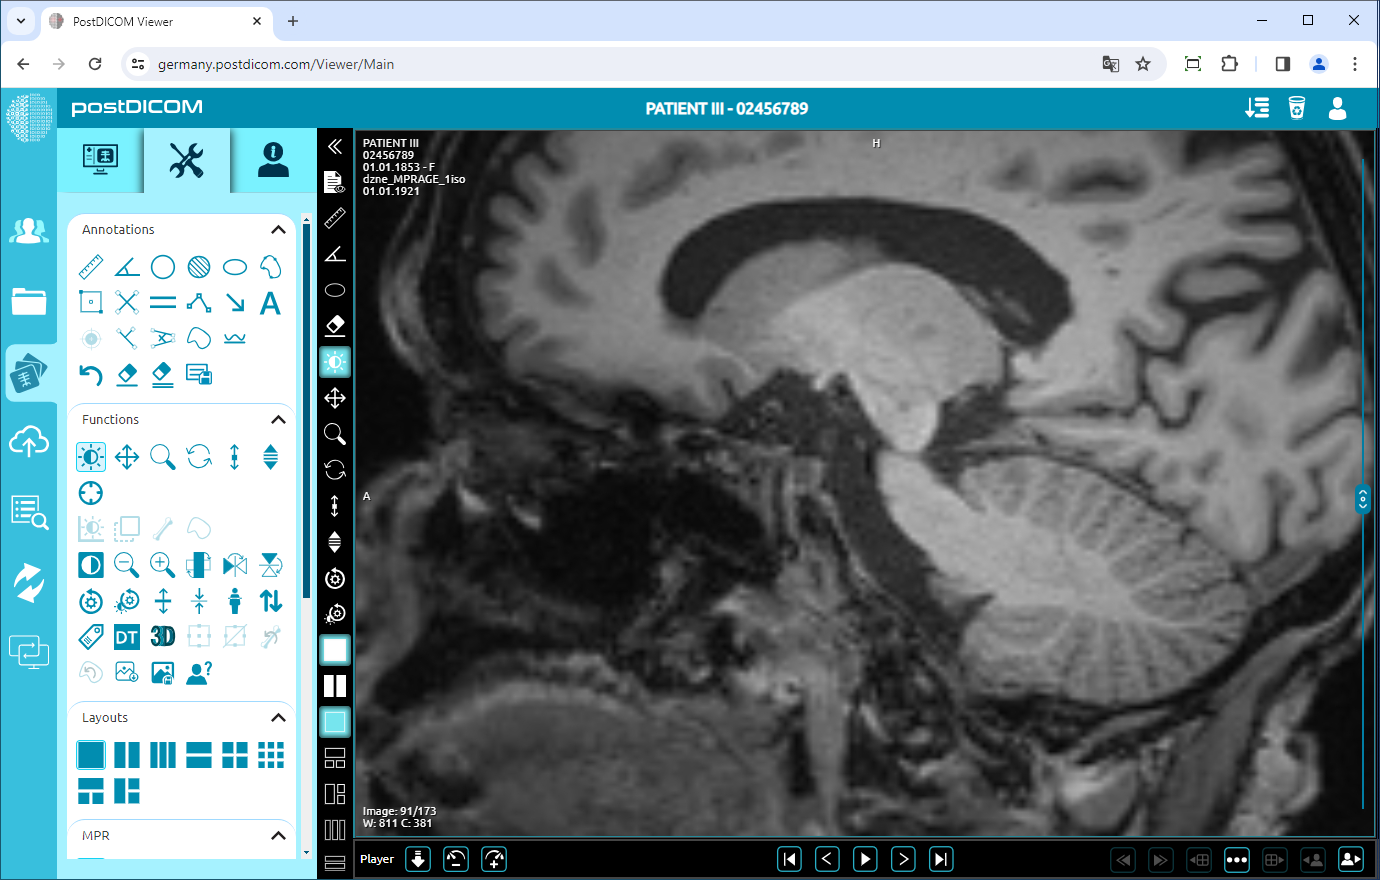

Zoom In/Out

Click on the “Zoom In” icon on the left side of the page to zoom in on the image by one level.

After clicking, the image will be one level bigger. The more you click, the image will be bigger.

To zoom out the image by one level, click on “Zoom Out” icon on the left side of the page.

After clicking, you will see that the image will be one level smaller. The more you click, the image will be smaller.